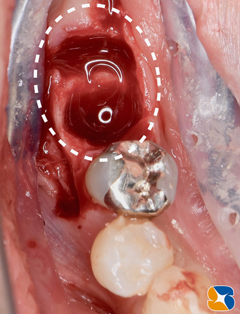

インプラント移植直後の状態。周囲の骨は抜歯の影響で、スカスカ空洞があります。

吸収性の人工骨に患者様御自身の血液で製作したコラーゲンとフィブリンの塊を混ぜて、不足している

骨の部分に添加しました。

コラーゲンの塊をシート状に圧縮して確実な骨の再生を促します。

当院でインプラント施術を受けられる方には、一連の作業は無料でおこなっています。